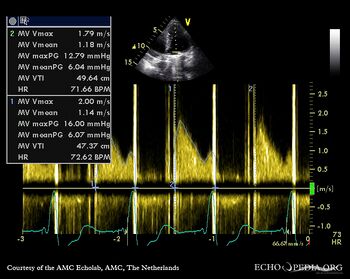

| Continuous-wave Doppler signal of transmitral flow | A4CH with Color Doppler: transtricuspid flow |